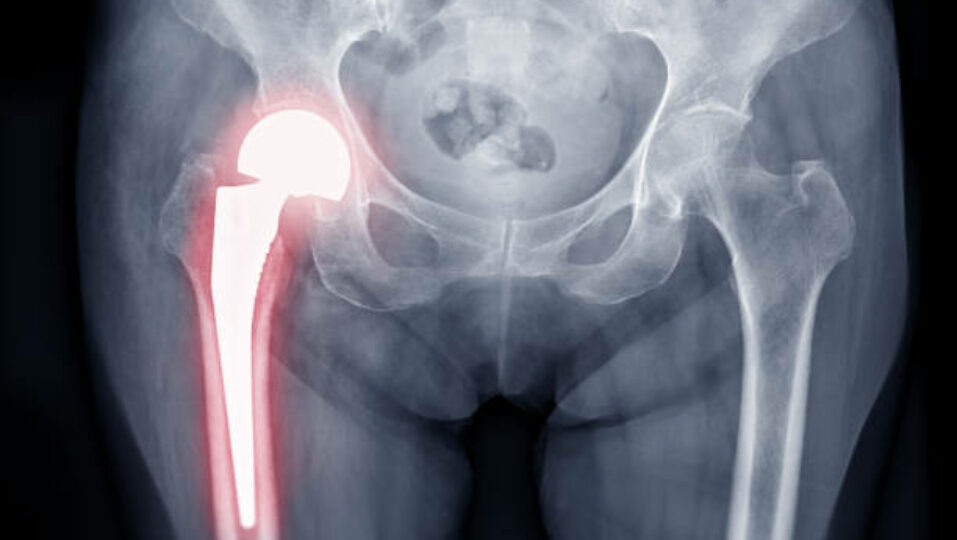

Hip replacement surgery, also known as total hip arthroplasty, is a highly effective procedure for individuals experiencing severe hip pain, stiffness, and limited mobility due to arthritis, injury, or degenerative joint conditions. The surgery replaces damaged bone and cartilage in the hip joint with high-quality prosthetic components made from metal, ceramic, or medical-grade plastics. These implants replicate the natural movement and function of a healthy hip, allowing patients to regain smooth, pain-free motion, whether through a total replacement (ball and socket) or partial replacement targeting the affected area.

The procedure begins with a comprehensive pre-surgical evaluation, including imaging studies, bone health assessment, and joint function analysis. During surgery, damaged areas of the hip are removed and replaced with customized implants designed for optimal stability and motion. Postoperative care focuses on early movement, guided physical therapy, and gradual strengthening of surrounding muscles. Most patients begin gentle exercises within a day or two, promoting circulation and preventing stiffness, while continuous monitoring by our orthopedic and rehabilitation team ensures proper healing and maximum recovery.

Modern hip implants are durable and can last 15–20 years or more with proper care, activity management, and regular follow-ups.